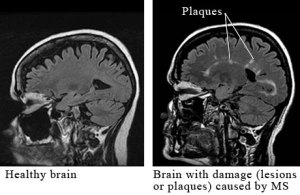

So, the doctor ordered MRIs of my brain, my neck, and my upper back to check for the presence of lesions on my nerves.  These lesions, if they exist, would be indications that my body is attacking the protective covering of my nerves.  If there are no lesions, like the photo on the left, then it is likely that my symptoms are due to another cause. If there are lesions, like the photo on the right, then….I don’t know.  I’ll keep on keeping on.  Drink water and keep marching.  Reach out in faith that the God who made me is also the God who heals me, no matter what diagnosis ends up coloring my chart.  I’m still me, and I’m very much alive and kicking.

The doctor should have results in the next couple of days, and I’ll learn if I have those white blotches or not.  Either way it will be kind of interesting to look at a picture and know that it is really a rendering of my brain….assuming there’s still one in there, of course!